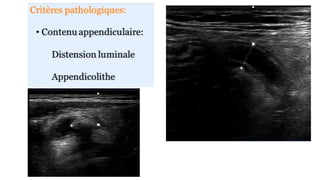

APPENDICITE

– Appendice de D> 6mm

– La paroi est épaissie et prise de

contraste

– Appendicolithe

– Infiltration de la graisse (péri cæcale,

pariétocolique)

Appendicitis : US